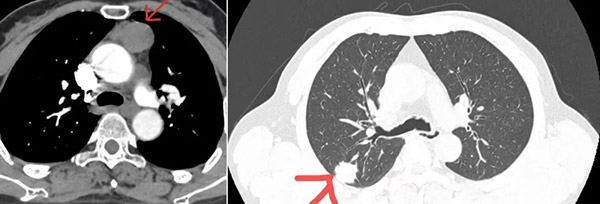

面对年近七旬患者“右肺上叶占位,前纵隔肿物”的检查结果,是依照常规方式行多次手术切除,还是为了减少患者损伤挑战“一次性”解决全部问题?沈阳市第六人民医院胸心外科主任舒健毅然选择了后者。

“看胸部CT检查结果,您右肺上叶占位、前纵隔肿物,考虑是肿瘤,需要手术切除……”听着舒主任的说明,王大哥瞬间觉得天都塌了,一家人陷入深深的焦虑之中。

“如 果采取传统的手术方式需要开胸,甚至得劈开胸骨,即便是非开胸的多孔胸腔镜手术,也要分多次进行,不仅费用较高,患者身体也会遭受多次损伤,不利于恢 复。”站在患者的角度考虑,舒主任决定通过单孔胸腔镜为王大哥一次性行右肺上叶切除术、纵隔淋巴结清扫术、纵隔肿物切除术,最大限度减少痛苦、降低开销。

经过详细的术前检查,王大哥接受了这台改变他命运的手术。单孔胸腔镜手术的难度本身就要比多孔的高,并且王大哥的病变位置靠上,操作空间更小,同时肿物位于纵隔深处主动脉弓上,周围都是心肺大血管,手术的风险陡增。术中,舒主任精准操作、步步为营,最终将肿物顺利切除。

经术后病理检验,王大哥右肺上叶腺癌、纵隔支气管囊肿,舒主任建议其后续进行基因检测,争取靶向治疗。得知结果后,悬在王大哥和家人心头的一块石头终于落了地。与此同时,王大哥的恢复情况也令人欣喜,术后4天拔除了胸腔引流管,第6天便顺利出院。